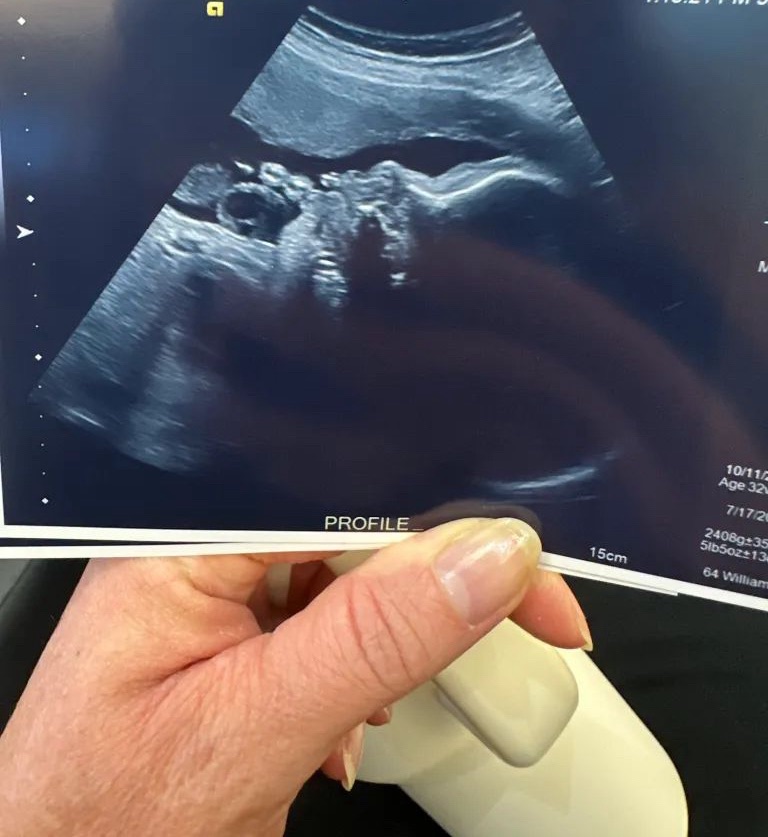

We just went in for a “growth” ultrasound on Tuesday — which is common when babies are in the 96th percentile. And she is doing wonderfully! She’s in the correct “head-down” position, and all cute and cuddled up, nice and cozy in there!

And as for her size, she is measuring at 5 and a half pounds already…which normally for a 33 week baby, they are about 4 pounds 3 ounces. She’s nearly a pound and a half ahead for her gestational age — still measuring in the 91st percentile!

So right before the ultrasound — literally as I was walking into the exam room — I shoved a date into my mouth and ate it, just to give her a little jolt of energy, to see if I could wake her up for the ultrasound, and sure enough…she was! We could literally see her eyes open and blinking!

And it was the cutest thing — she even yawned on the ultrasound! And we could see her little tongue swallowing the amniotic fluid (apparently enjoying that little jolt of sweetness from the date!) How absolutely precious! What a miracle life is! To think that our little lady is in there swimming around, drinking, yawning, blinking — God is just amazing the way He has created the female body to create life, and the beautiful formation that occurs during those nine months inside the womb!!